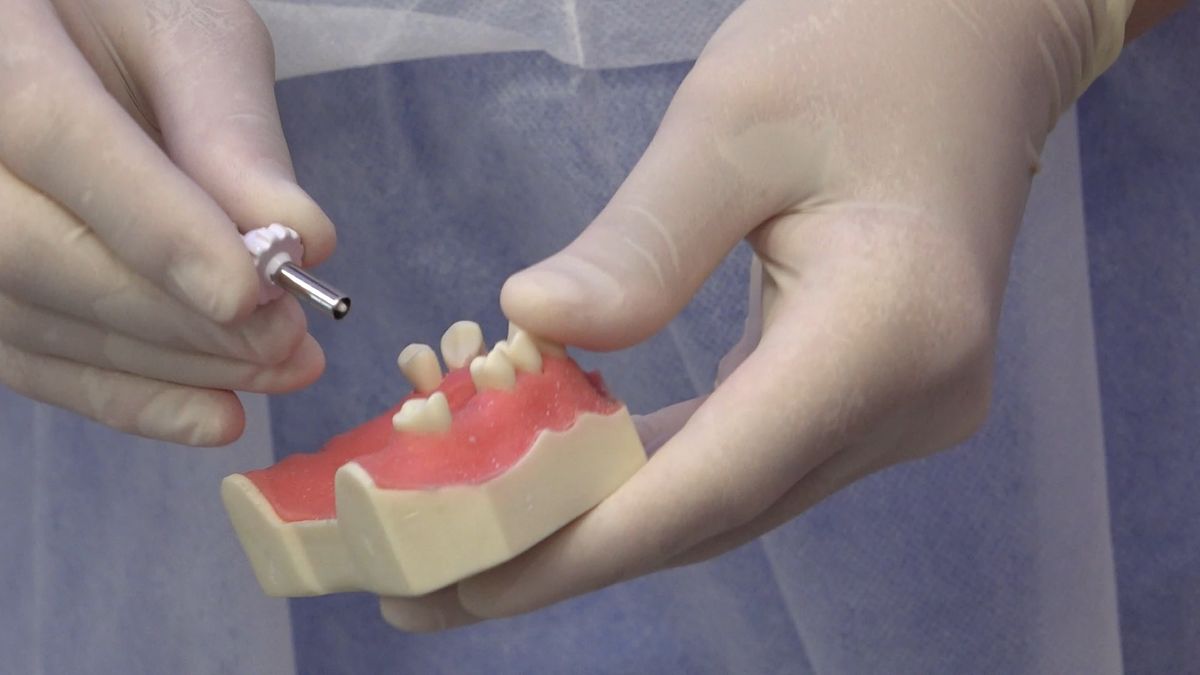

Tematem przewodnim 3 Sesji X Sezonu Practiculum Implantologii była protetyka na implantach. Lekarze przeprowadzili wiele procedur implantoprotetycznych pod kierunkiem dr n.med. Violetty Szycik, w tym oddanie prac przykręcanych i odsłonięcie implantów. Pod kierunkiem dr Małgorzaty Piotrowskiej wykonywali pobieranie wycisków z poziomu implantów tradycyjnie i za pomocą skanera. Zabiegi i ćwiczenia poprzedziły wykłady, które przeprowadził także technik dentystyczny Marek Wiligała.